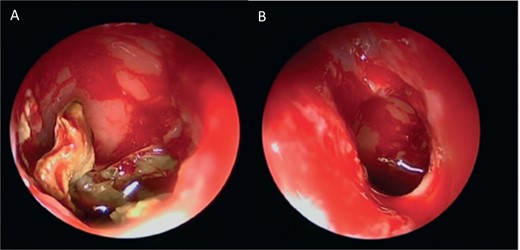

A 12-year-old young girl with relapsing acute myeloid leukemia presented with fever, headache, and left maxillary facial pain. Her symptoms were associated with blood-tinged nasal discharge. Nasal endoscopic examination showed friable ulcerative mucosa of the left middle turbinate and osteo-meatal complex which raised a clinical suspicion of invasive fungal sinusitis. Thus, a contrast-enhanced CT scan (CECT) (Fig. 3) was necessary which showed enhancing left maxillary sinus opacity suggestive of acute invasive fungal sinusitis. The patient underwent urgent endoscopic medial maxillectomy with removal of invasive fungal debris (Fig. 4) along with debridement of left middle turbinate, medial maxillary wall, and orbital floor. A diagnosis of invasive mucormycosis was confirmed by histopathology. The patient was started on aggressive treatment in the form of intravenous and oral antifungal medications. She was regularly followed up for the next 5 years with no evidence of recurrence.

Intra-operative endoscopic maxillary examination (A and B) showing invasive fungal debris.